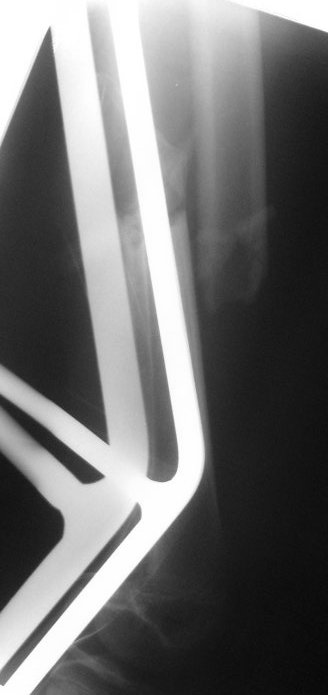

Несвежий перелом бедра

На сегодняшний день вот такая картина: девочка, 13 лет, 3 недели на скелетном вытяжении по поводу оскольчатого перелома нижней трети левого бедра.

Сейчас инфекцию "победили", отек бедра за последние дни значительно спал, но имеется укорочение 2 см, отломки уже "прихватились", патологической подвижности нет.

Имелось опасение, что "разнесет" инфекцию в зону перелома. Вроде пронесло.

Что применить?

Растянуть в аппарате (одномоментно/дискретно)?

TEN или гвоздь?

Оставить так?